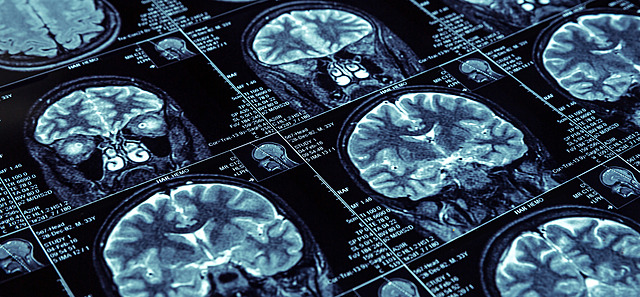

RESONANCIA MAGNETICA(RM) es una técnica que utiliza un campo magnético y ondas de radio para crear imágenes detalladas de los órganos y tejidos del cuerpo.

La mayoría de las máquinas de RM son grandes imanes con forma de tubo. Cuando te recuestas dentro de una máquina de RM, el campo magnético realinea temporalmente los átomos de hidrógeno en tu cuerpo. Las ondas de radio hacen que los átomos alineados produzcan señales muy débiles, que se usan para crear imágenes transversales de resonancia magnética,. La máquina de RM a también puede usarse para producir imágenes tridimensionales que pueden verse desde diferentes ángulos.